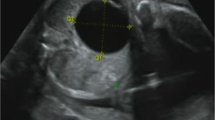

The presence of hyperechogenic kidneys, with multiple bilateral cortical cysts at US examination, associated with a moderate alteration of renal function, were suggestive of ciliopathy. Hepato-biliary scintigraphy showed no passage of bile. A liver biopsy was performed, revealing PILBD with biliary stasis (Fig. 1). The association of cholestasis and PILBD, other than the renal involvement, led us to reconsider the diagnosis of AGS and to perform genetic tests for liver cholestatic diseases.

Histology of liver biopsy

a Paucity of intrahepatic bile ducts with mild Kupffer cell activation, mild hepatocitic polymorphism, focal eosinophilic degeneration with a Councilman body; compatible with lobular light hepatitis. H&E 250X. b Interlobular portal tract with a ductular reaction resembling a ductal plate malformation. Cytokeratin 7250X.